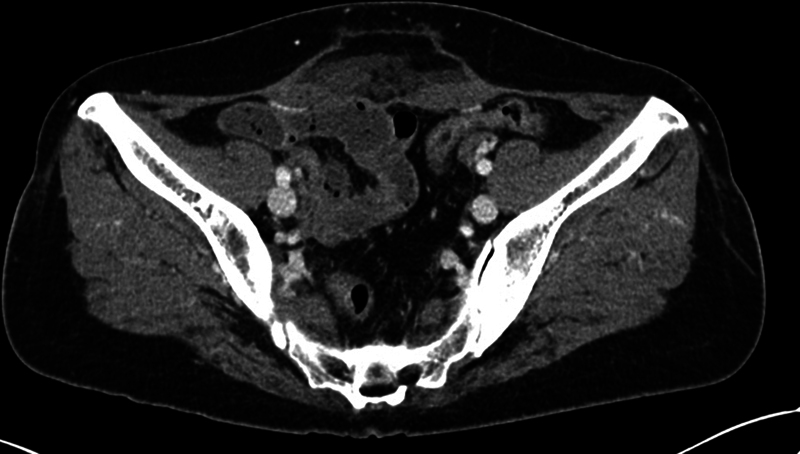

尽管许多研究报告了高强度聚焦超声(HIFU)疗法的安全性和有效性,但人们仍然担心内脏损伤。然而,关于 HIFU 治疗后腹壁疝的报道却很少见。我们报告了三例子宫腺肌症或子宫肌瘤患者在接受 HIFU 治疗后出现腹壁疝但无皮肤损伤的病例。由于症状模糊、临床怀疑不充分以及未及时进行适当的影像检查,诊断往往被延误。应将腹壁疝视为 HIFU 治疗后可能出现的并发症,当患者出现异常腹部肿胀和/或疼痛,且持续时间超过术后数月时,就应怀疑腹壁疝。

Although many studies reported the safety and efficacy of high-intensity focused ultrasound (HIFU) therapy, there are still worries about internal organ injury. However, reports of abdominal wall hernias after HIFU therapy are rare. We present three cases of abdominal wall hernias without skin injury after HIFU therapy in uterine adenomyosis or fibroids. The diagnosis was often delayed because of vague symptoms, inadequate clinical suspicion, and delayed proper image studies. Abdominal wall hernia should be recognized as a possible complication after HIFU and be suspected when the patient presents with unordinary abdominal swelling and/or pain that lasts for more than a few months after the procedure.